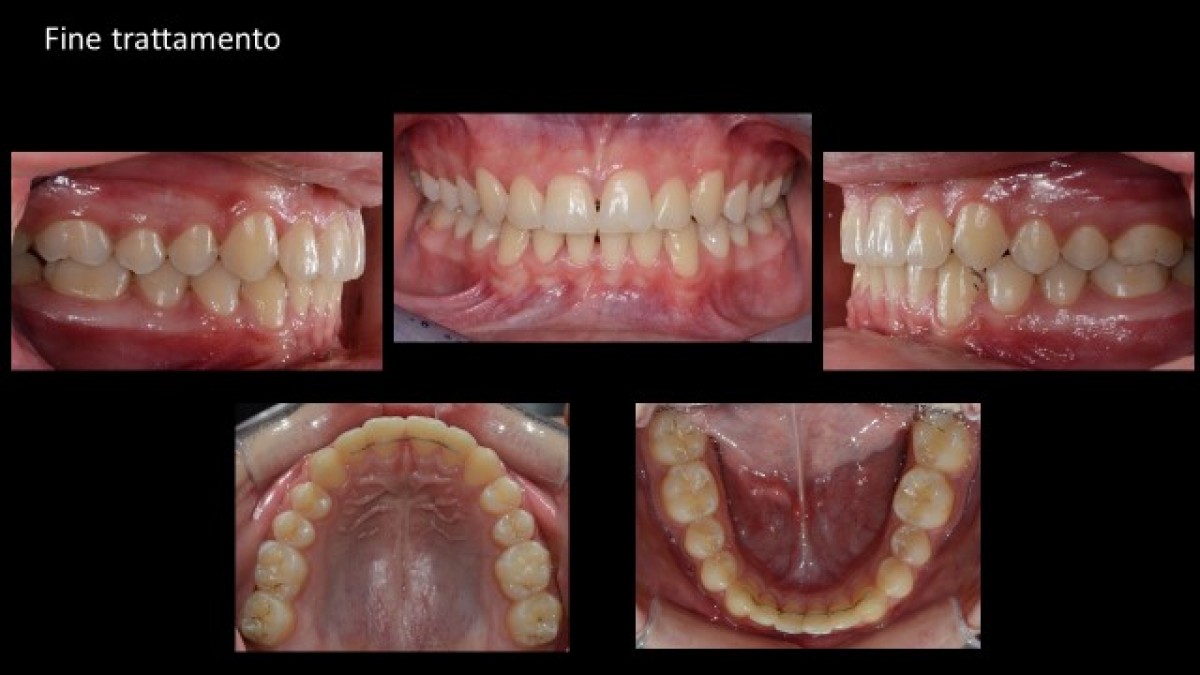

Final cephalometric analysis and treatment start-end image overlap show that, in this case at least, the personalised braces were effective in correctly positioning and angling the upper and lower incisors (fig. 16).